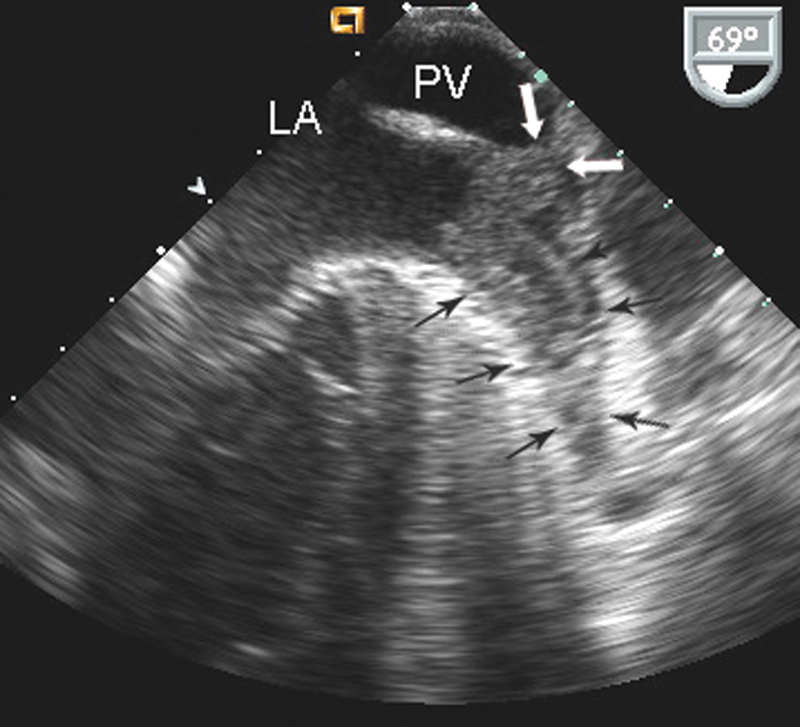

فحوصات تشخيصية لبعض امراض القلب والشرايين التاجية